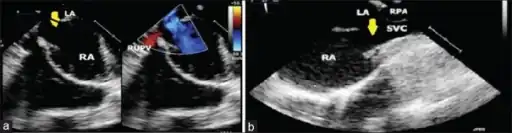

Image shows sinus venosus atrial septal defect and partial anomalous pulmonary venous connection

They can occur near the superior vena cava or inferior vena cava, but the former are more common.[2]

They can be associated with anomalous pulmonary venous connection.[3]